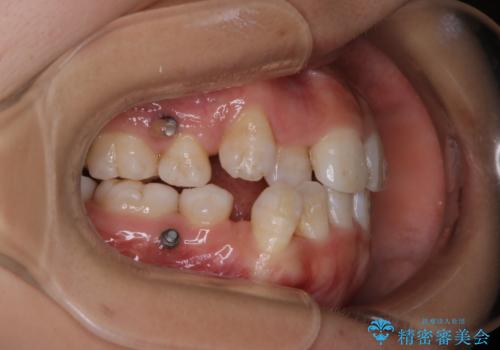

インビザライン単独での抜歯矯正治療

- 当院にてインビザライン治療を行っていた同僚の方からのご紹介でいらした方です。楽器を演奏されるとの事で、インビザラインによる矯正治療をご希望されました。治療の途中で一時的にワイヤー矯正に切り替える可能性もあることもご了承頂いた上で治療を行いました。

1日20時間以上、正しくインビザラインを使用して頂いたおかげで、ワイヤーに切り替えることなく矯正治療を終了することが出来ました。抜歯症例でしたが比較的短期間で見た目が劇的に改善し、大変喜んでいただけました。